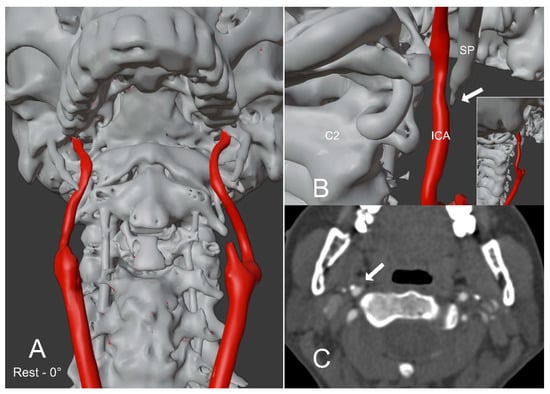

Figure 1.

Patient with Eagle Syndrome in a rest position. (A,B) show a 3D reconstruction model of a patient with. The model was created from the rest position CTA of the head and neck. The right styloid process abuts the ipsilateral internal carotid artery (arrow in (B)). The enclosed image in (B) represents a postero-lateral perspective with a zoomed-out view. (C) shows the CTA image of the styloid process abutting the ipsilateral internal carotid artery (arrow). SP = Styloid process; ICA = Internal carotid artery; C2 = C2 Vertebral body.